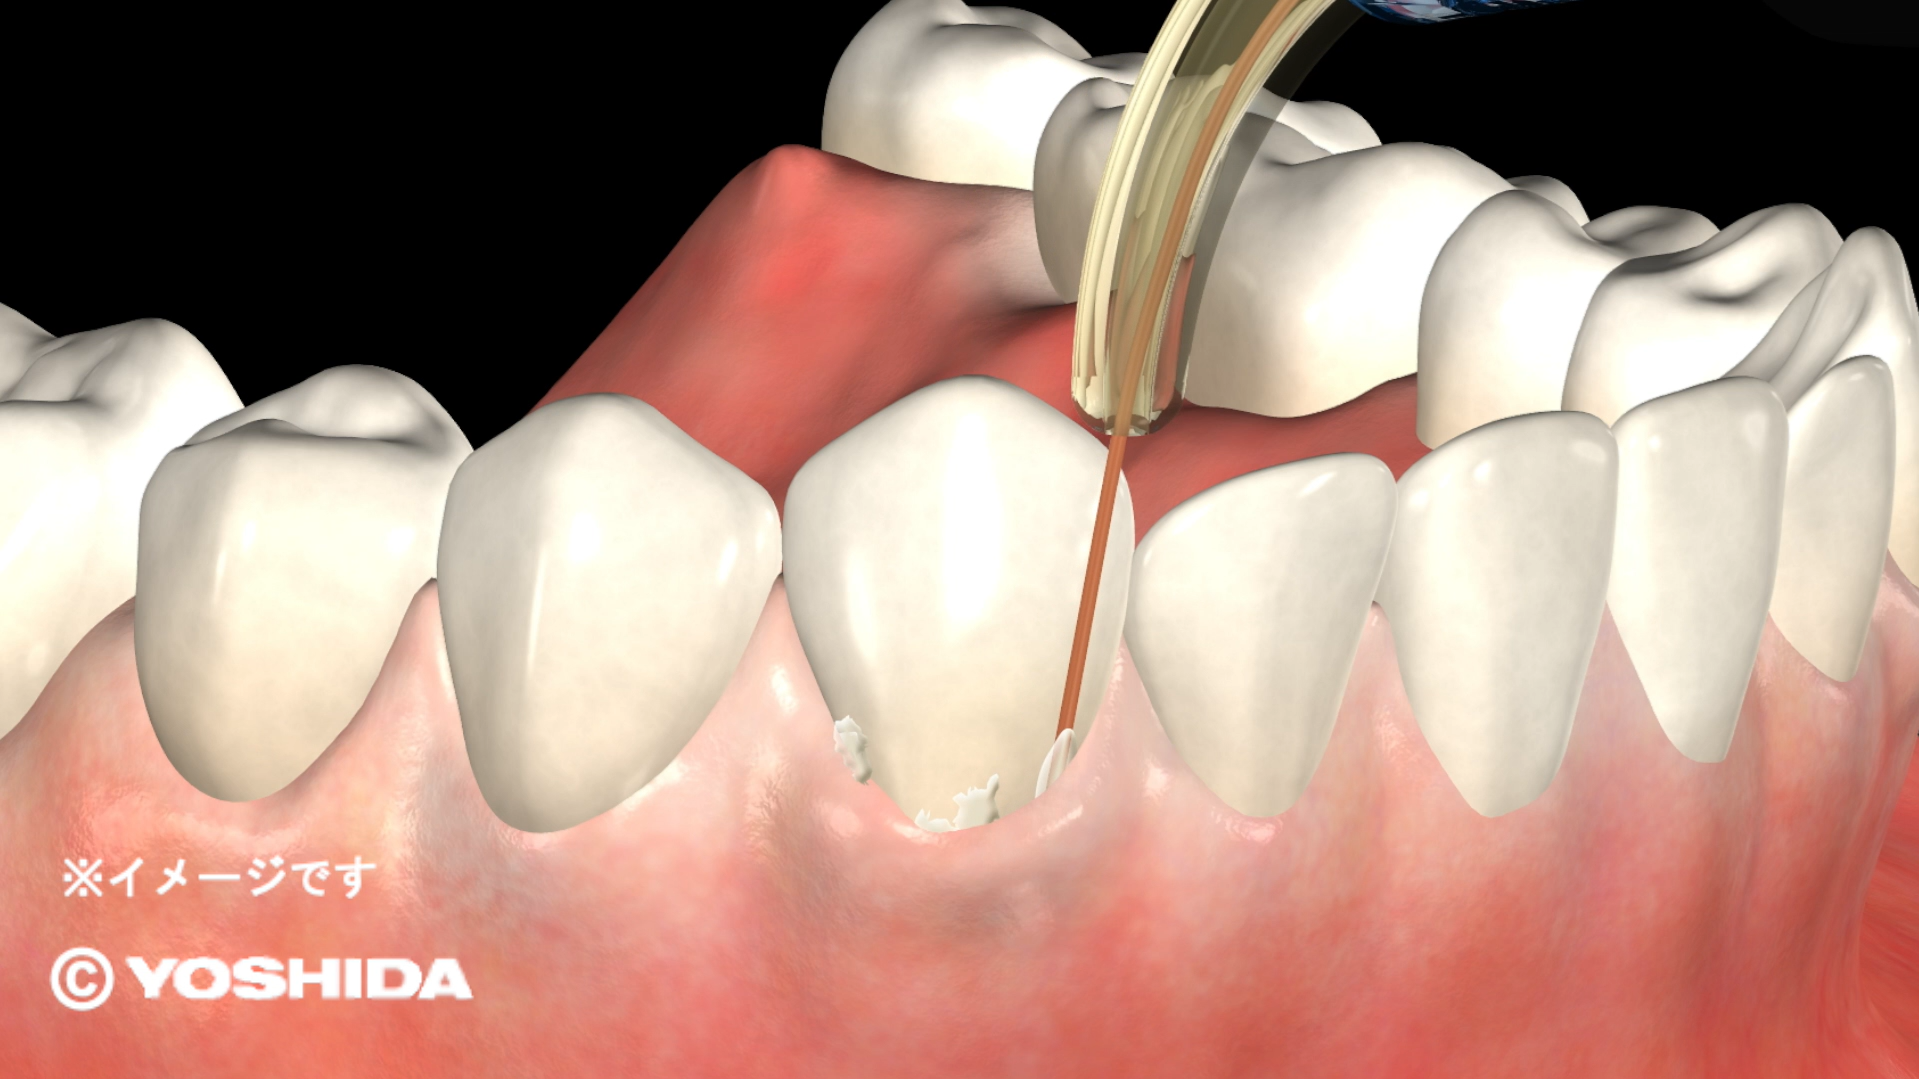

(1)オペレーザー商品とは、株式会社吉田製作所が製造する歯科用レーザー機器であって、「オペレーザー」を販売名に含む商品をいいます。